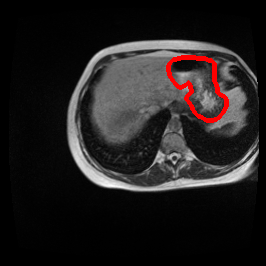

Ghosting Artifact

MRI GMAIMMbench Organ Recognition - Abdomen

Ghosting Artifact - L0 (Original)

L0

L0 (Original)

Question

Observe the MRI image. Can you identify the organ in the highlight area?

A fat B stomach C optic cup D gallbladder E optic disc

Ground Truth: B. stomach